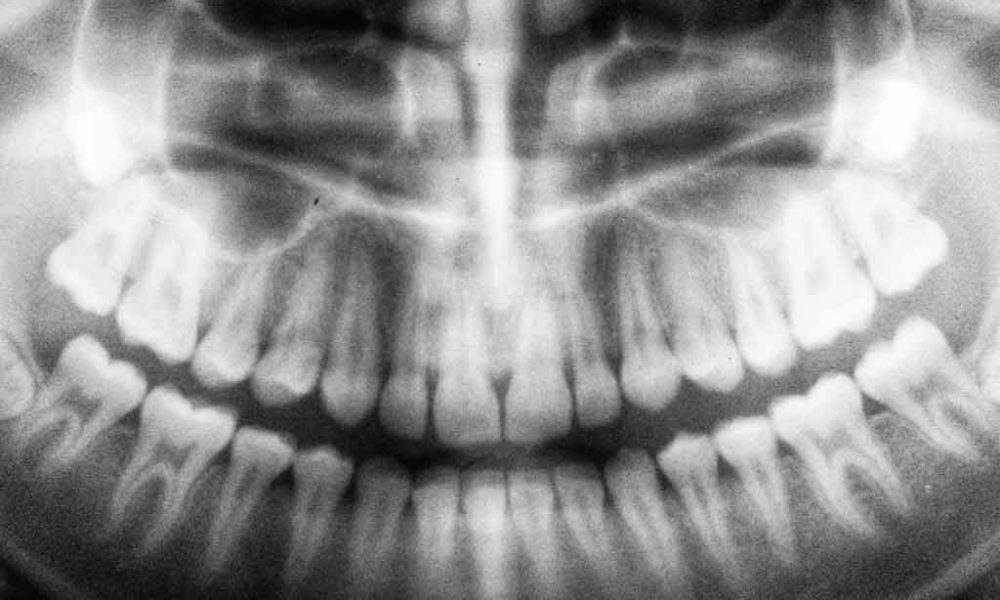

If your dentist still uses the obsolete method of putting a piece of cardboard-covered film between your teeth and telling you to, “bite down,”…

Along with many technological advances, dentistry has evolved towards becoming more digital in the past few years. The newest systems include computerized…